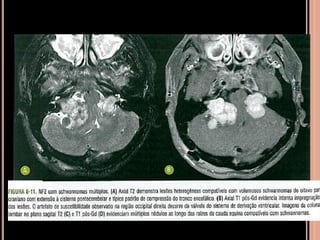

 Schwannomas volumosos se estendendo para a

cisterna pontocerebelar com intensa impregnação

pelo Gd; na sequência em T2 tem hipersinal

heterogêneo;

 Múltiplos nódulos, em T1 pós contraste importante

realce compatíveis com schwannomas;